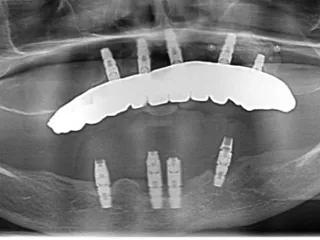

Seguida de la colocación inmediata de 4 implantes Straumann TLC™, ∅ 3,75 mm x 10 mm (44, 42, 32), ∅ 3,75 mm x 12 mm (34) SLActive®, Roxolid® y restauración provisional inmediata.